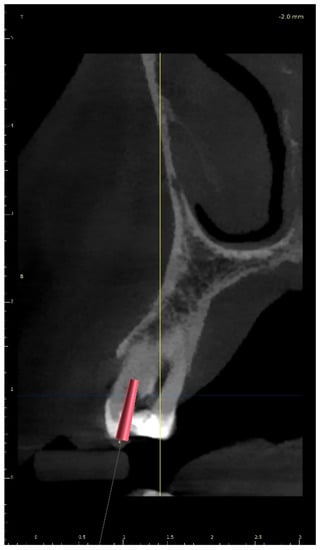

A 21-year-old female patient reported to the endodontic specialist complaining of moderate pain upon percussion of her maxillary central left incisor (tooth 21), experienced for several weeks. The patient was healthy and had no general or chronic diseases. Her dental history revealed that she had experienced dental trauma a few years earlier. The clinical examination revealed a slightly discoloured maxillary left central incisor, tenderness to percussion, a negative response to the pulp sensibility test (cold test), and moderate pain during soft tissue palpation in the apical region of the maxillary central left incisor. Radiographic images revealed the pulp canal calcification and an absence of the canal light that extended to the middle. A CBCT scan was performed (CS 8100 3D, Carestream, 50 × 50 mm) that confirmed canal calcification. The root canal lumen was visible 7.58 mm from the apex (Figure 8). Due to the possible risk of higher tooth substance loss and perforation during endodontic access, we decided to perform the endodontic treatment with guided access.

Figure 8. CBCT sagittal view image revealed a 7.58-mm-long visible part of the root canal on tooth 21 (FDI).